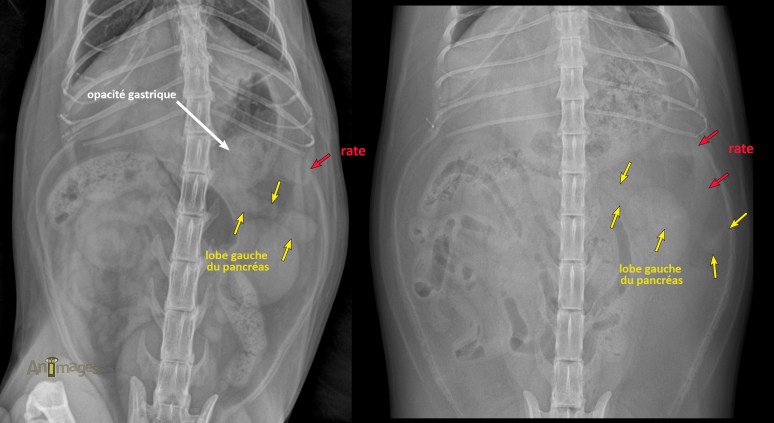

L’opacité partiellement superposée à la rate et au pôle crânial du rein gauche représentait effectivement le lobe gauche du pancréas. Comme le démontrent l’image de gauche du chat de l’article initial et celle de droite appartenant à un autre chat, on constate que ce lobe peut être observé chez des chats obèses lorsque le petit intestin et le côlon sont déplacés vers la droite, libérant cet espace. Dans le cas présenté la semaine dernière, une exploration chirurgicale a été réalisée. Le pancréas paraissait alors épaissi et irrégulier, mais les biopsies n’ont pas révélé d’anomalie histologique. La palpation de l’estomac a révélé la présence d’une masse tissulaire intragastrique pédiculée qui s’est avérée être un polype (i.e. hyperplasie adénomateuse), expliquant l’opacité présente au niveau du corps et du fondus gastrique (image de gauche).